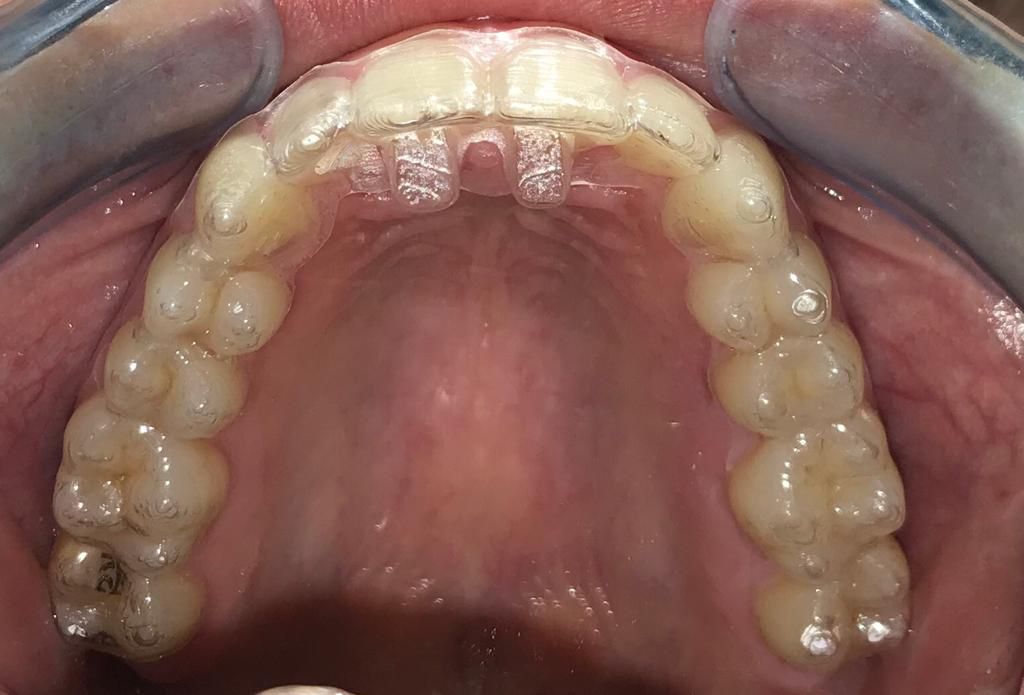

Podemos observar que los attachments son super cómodos y son casi imperceptibles al ojo.

Tal como vimos anterirmente los attachments (o botones) son formas geométricas que se agregan a la cara vestibular de algunos dientes, para incrementar la acción de la placa alineadora. Estos botones se crean adhiriendo un material de obturación en los dientes señalados, mediante un molde enviado por KeepSmiling.

Vemos que los objetivos principales de la colocación de los attachments incluyen facilitar el anclaje de la placa alineadora aumentando su acción; ayuda tanto la intrusión de los dientes como a la extrusión; permite mover las raíces colocando un torque sobre la corona; y rotar dientes con forma cilíndrica. Además, aumenta la retención de la placa alineadora en coronas cortas y ayuda a reducir la inclinación de la corona hacia un brecha.